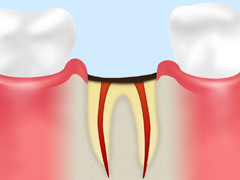

C3:神経まで進行

虫歯が神経にまで達した状態。普通にしていても激しい痛みを感じます。

歯の神経を除去し、薬を詰めたあとにクラウン(被せ物)を被せます(根管治療)。

C4:歯根にまで進行

虫歯が歯根に達した状態。神経が死んでいるため痛みは感じませんが、化膿すると再度激しく痛みます。

ほとんどの場合において、抜歯が必要です。歯を失った部分には入れ歯やインプラントで補完します。